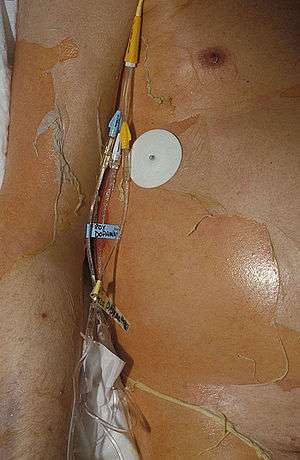

Nearly all people with TEN have oral, eye and genital involvement as well. Painful crusts and erosions may develop on any mucosal surface.[11] The mouth becomes blistered and eroded, making eating difficult and sometimes necessitating feeding through a nasogastric tube through the nose or a gastric tube directly into the stomach. The eyes can become swollen, crusted, and ulcerated, leading to potential blindness. The most common problem with the eyes is severe conjunctivitis.[12]

The primary treatment of TEN is discontinuation of the causative factor(s), usually an offending drug, early referral and management in burn units or intensive care units, supportive management, and nutritional support.[3]